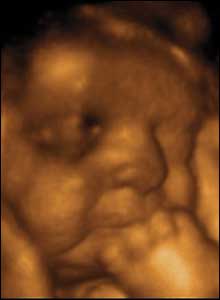

10 weeks gestation, 60mm from crown to rump.

2 of 10

At ten weeks gestation, this foetus can move her arms and legs with a range of movements that are fluid and supple.